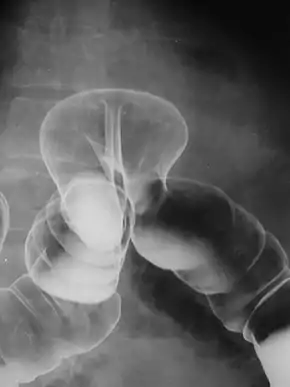

X-ray of colonic herniation

By far the most common hernias (up to 75% of all abdominal hernias) are inguinal hernias, which are further divided into the more common indirect inguinal hernia (2/3, depicted here), in which the inguinal canal is entered via a congenital weakness at its entrance (the internal inguinal ring), and the direct inguinal hernia type (1/3), where the hernia contents push through a weak spot in the back wall of the inguinal canal. An indirect inguinal hernia and a direct inguinal hernia can be distinguished by their positioning in relation to the inferior epigastric vessels. An indirect hernia is situated laterally to these vessels, whereas a direct hernia is positioned medially to them. Inguinal hernias are the most common type of hernia in both men and women. In some selected cases, they may require surgery.